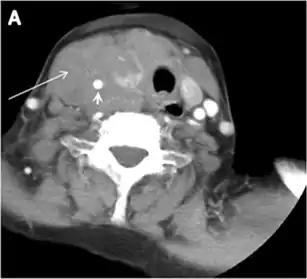

Fig. 9. A 58-year-old male patient with persistence PTC at thyroid bed with hypervascular nodal metastasis. a–c Transverse greyscale and colour Doppler neck ultrasound demonstrate hypoehoic soft tissue in the left thyroid bed (white arrow in a). There are a heterogeneous enlarged lymph nodes at level 2 and 3 with markedly increased vascularity (white arrow in b and c). d–f Enhanced axial CT images of the neck demonstrate a 2.7 × 1.4 cm hypodense soft tissue lesion anterior to the left carotid sheath (white arrow). There are left-sided enhancing abnormal and enlarged lymph nodes at cervical level 2 and 3 (black arrows).[1]

The likelihood of positive anatomic imaging is greater when serum Tg is >10 ng/mL. A diagnostic CT scan adds additional value to neck US in detecting central compartment macro-metastases in the mediastinum and retro-tracheal area. According to the recent American Thyroid Association guidelines, an upper chest and neck CT scan with IV contrast should be obtained when: 1) neck US is inadequate in visualizing possible local nodal disease (high Tg, negative neck US, and RAI imaging); 2) US is not able to delineate the disease completely, as in the case of bulky recurrent nodal disease; or 3) evaluation of possible recurrent invasive disease is needed (Figs. 7, 88 and and9).9). CT scans are also the most sensitive diagnostic tool for the detection of pulmonary micro-metastases. Many of the neck US features that are considered as suggestive signs of disease recurrence are also applicable to CT examination. These signs might include sizable rounded nodules in the thyroid bed, fine calcifications, or cystic change.[1]